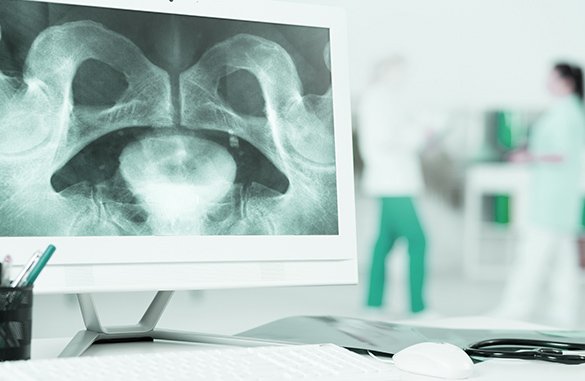

Chrząstka stawowa w zdrowym stawie działa jak amortyzator: rozkłada nacisk, umożliwia płynny ruch i chroni kość. Gdy procesy niszczenia przeważają nad odbudową, chrząstka traci elastyczność, staje się chropowata i pęka.

Odsłonięta kość ulega stwardnieniu (sklerotyzacji) i tworzy wyrośla kostne – osteofity, które ograniczają ruchomość i powodują ból. W stawie rozwija się również stan zapalny błony maziowej, odpowiedzialny za obrzęk i uczucie sztywności.